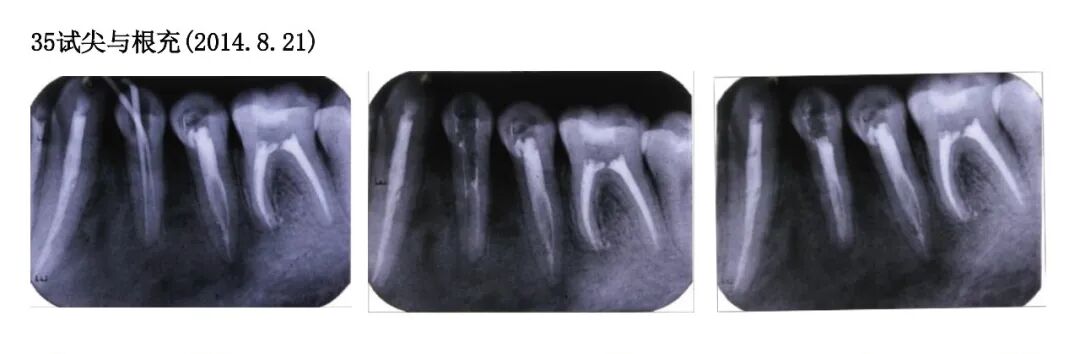

Pre-operativeX-ray examination

Trial apex and root filling for tooth 35 (2014.8.21)